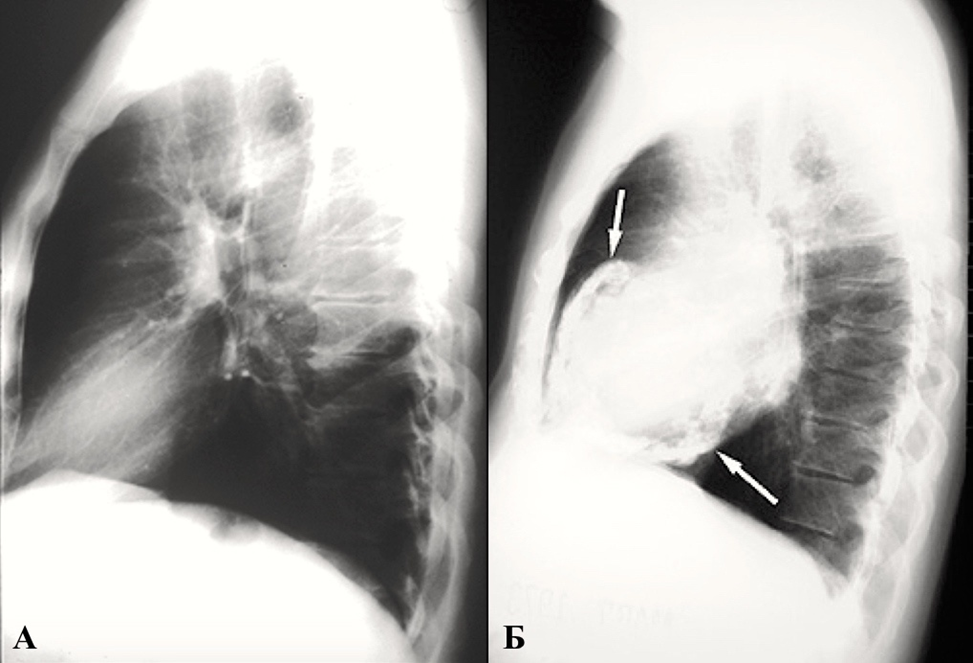

1. Рентгенография

Рентгенография позволяет заподозрить наличие экссудативного перикардита на основании быстрого увеличения тени сердца на рентгенограмме (если имеются серии предыдущих снимков или же при отсутствии в анамнезе болезней, которые могут приводить к кардиомегалии). При экссудативных перикардитах сердце принимает вид горизонтально расположенного овала, распложенного на диафрагме (симптом «фляжки с водой»). Такая конфигурация отличается от кардиомегалии, вызванной расширением всех камер сердца, когда тень увеличенного сердца имеет форму, более близкую к трапециевидной. В случае хронического перикардита с кальцинозом листков перикарда и конструктивного перикардита на рентгенограмме можно видеть участки выраженного обызвествления листков перикарда. Однако чувствительность рентгенографии в выявлении кальцификации листков перикарда уступает таковой КТ. Рентгенография может применяться для быстрой полуколичественной оценки изменений объема жидкости в перикарде на фоне консервативного или интервенционного лечения перикардитов. Этот метод оказывает помощь в тех случаях, когда перикардиты сочетаются с заболеваниями легких (пневмонии, туберкулез) или средостения.

При остром фибринозном перикардите прицельная рентгенография органов грудной клетки выполняется, как правило, с целью исключения патологии органов средостения и легких, которые анатомически близки к околосердечной сумке. В остальных же случаях исследование малоинформативное, по причине отсутствия каких-либо характерных изменений тени сердца [3, 152].

В то же время при подозрении на другие формы перикардита, рентгенография может стать дополнительным диагностическим инструментом [1, 3, 96]. Достигая умеренной чувствительности в 70%, она обладает низкой специфичностью — 41%, что делает невозможным использование этого метода в отрыве от клинической картины [1, 3, 149].

При констриктивном перикардите маленькое «неподвижное» сердце не меняет своего расположения при изменении положения тела или при дыхательной экскурсии. Сжатое сердце теряет свою талию и дифференциацию дуг, появляется неровность контуров, обусловленная многочисленными сращениями в перикардиальной полости. Выявляются небольшие желудочки при одновременном увеличении предсердий. Характерно отсутствие застоя по малому кругу.

Развитие «панцирного» сердца происходит в 25% случаев констриктивного перикардита. Обызвествленные участки лучше определяются на боковой и передней косой проекциях (Приложение А3, рис. А3-9) [1, 3].